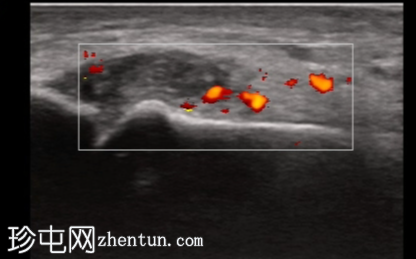

4.png

纵轴切面

第一跖趾关节纵轴切面

关节积液伴轻度滑膜增生。高回声不规则沉积物,符合尿酸钠晶体沉积的典型表现。彩色多普勒成像显示滑膜充血活跃,符合急性炎症活动。